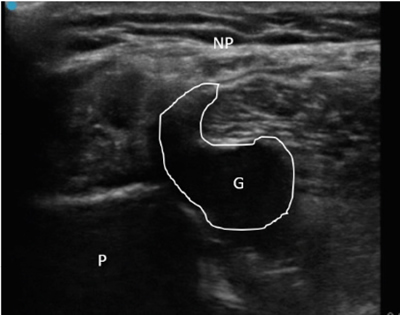

Neuropatía peronea secundaria a ganglión extraneural: revisión de literatura y propuesta de tratamiento. Caso no positivo

Este artículo presenta el caso de un paciente de 69 años con una neuropatía compresiva peronea secundaria a un ganglión, inicialmente interpretada como una radiculopatía L5. Este incorrecto enfoque supuso la sobremedicación del paciente, un mal control algésico, la realización de una discectomía L4-L5 innecesaria y una pobre evolución neurológica.

Un enfoque diagnóstico correcto y un abordaje terapéutico precoz habrían supuesto una mayor mejoría clínica e incluso una recuperación neurológica completa del paciente. Por ello, este caso sirve para resaltar: a) el valor de la ecografía en neuropatías periféricas como herramienta diagnóstica y pronóstica y el de la ecografía en gangliones como arma diagnóstico-terapéutica; b) el uso de las pruebas diagnósticas como apoyo a una exploración física exhaustiva, y no como diagnóstico en sí mismas, y c) la importancia de la publicación de casos no positivos para optimizar recursos, evitar repetir errores, reducir el sesgo de publicación y facilitar el inicio de proyectos de investigación.

Figura 1

Figura 2